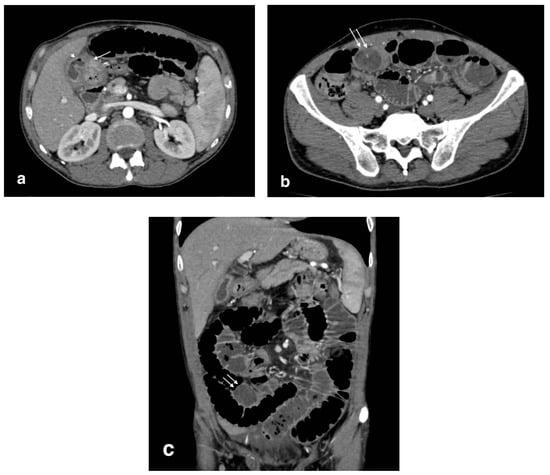

A pathological communication between the gallbladder and GI tract can develop in the setting of an acute cholecystitis, or after recurrent episodes, in which the formation of adherences favors the genesis of a fistula. Usually, the fistula develops between the gallbladder and the small bowel, most frequently in the duodenum, but other locations are possible, even if less common, such as in the stomach or colon [18]. MDCT scans, and in particular multiplanar reconstruction, should be performed to evaluate the continuity between the organs. Gallstone ileus is a rare complication in which a large gallstone (usually >2.5 cm), due to the formation of a fistula, migrates and impacts into the small bowel (most frequently in the distal ileum), leading to small bowel obstruction. CT is essential for diagnosis, through the evidence of Rigler’s triad (pneumobilia, small bowel obstruction, and large gallstone in the ileus in 79% of the patients) (Figure 6) [19]. After a gallstone is visualized within the extrabiliary GI tract, it is recommended to look for the presence of other gallstones outside the biliary system.

Figure 6.

Bilioenteric fistula (biliogastric) with gallstone ileus: (a): cholecystogastric fistula (arrow) with the presence of air in the gallbladder lumen (arrowhead); (b) axial image shows a large gallstone in the ileum (arrows) with small bowel overdistension (white arrows); (c) coronal image demonstrates an obstructive gallstone in the ileum (arrows) with small bowel overdistension.